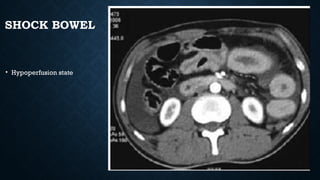

SHOCK BOWEL

• Hypoperfusion state